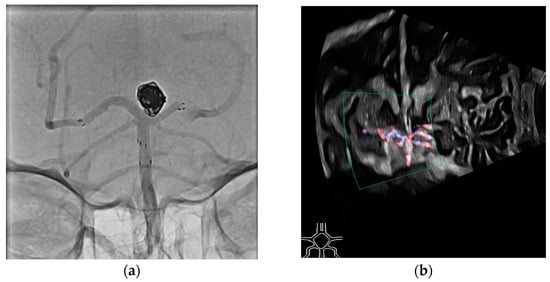

In the second case, a patient experienced a SAH due to a ruptured basilar tip aneurysm. The aneurysm was treated with coil embolization and a Y-stent. Given the early postoperative period, dual antiplatelet therapy was not feasible. Ultrasound was used to monitor the patency of the stent and to exclude in-stent thrombosis (Figure 9).

Figure 9.

Digital subtraction angiography (a) and duplex ultrasound (b) of the basilar artery treated with a Y-stent. Clear perfusion is visible in the duplex ultrasound, and in this case, the need for follow-up CT angiography to rule out arterial occlusion was avoided. This patient also recovered well and was soon transferred to rehabilitation.